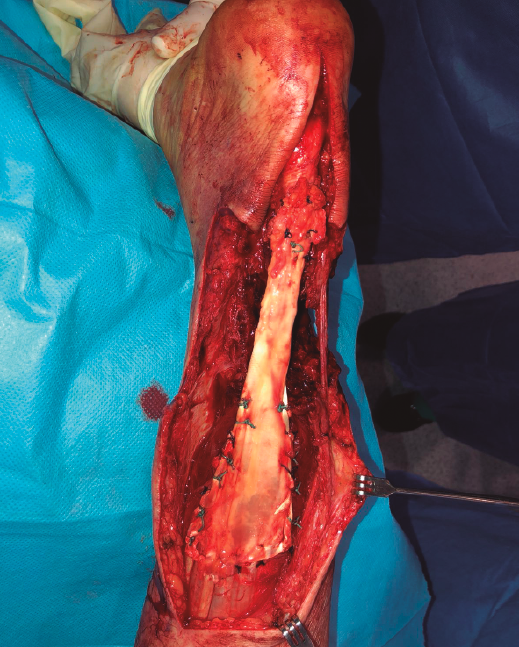

Se objetivó un defecto de 15 cm en el tendón calcáneo (Figura 3). Se aproximaron los bordes de la herida con seda quirúrgica y se realizó un vendaje compresivo.

La fijación se obtuvo a través de una sutura de tipo Krackow en la unión miotendinosa proximal y sutura término-terminal a nivel distal, al existir muñón distal suficiente (Figura 5). De forma simultánea, se realizó la cobertura cutánea con un colgajo fascio-cutáneo vascularizado del muslo del paciente (Figuras 6A, 6B y 6C).

Figura 5. Fotografía intraoperatoria. Muestra la sutura proximal de tipo Krackow y la anastomosis distal con muñón de tendón remanente.